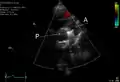

PDA is usually diagnosed using noninvasive techniques. Echocardiography (in which sound waves are used to capture the motion of the heart) and associated Doppler studies are the primary methods of detecting PDA. Electrocardiography (ECG), in which electrodes are used to record the electrical activity of the heart, is not particularly helpful as no specific rhythms or ECG patterns can be used to detect PDA.[7]